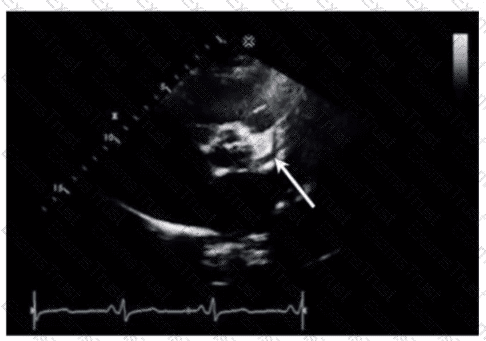

What is indicated by the arrow on this video clip?